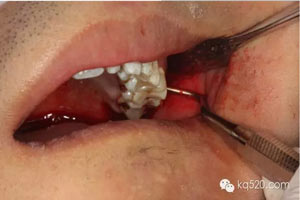

圖1.術前口內(nèi)像:上頜結節(jié)后份有一溢膿的瘺道,看不到28。

圖4.頰側局部無痛浸潤麻醉